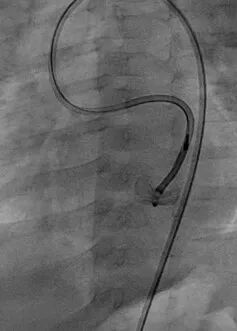

03

从右侧股动脉引入5F PDA鞘直至瘘口,经鞘管将12 mm的AMPLATZER Plug(AVP Ⅱ)1枚栓塞瘘口。

图片